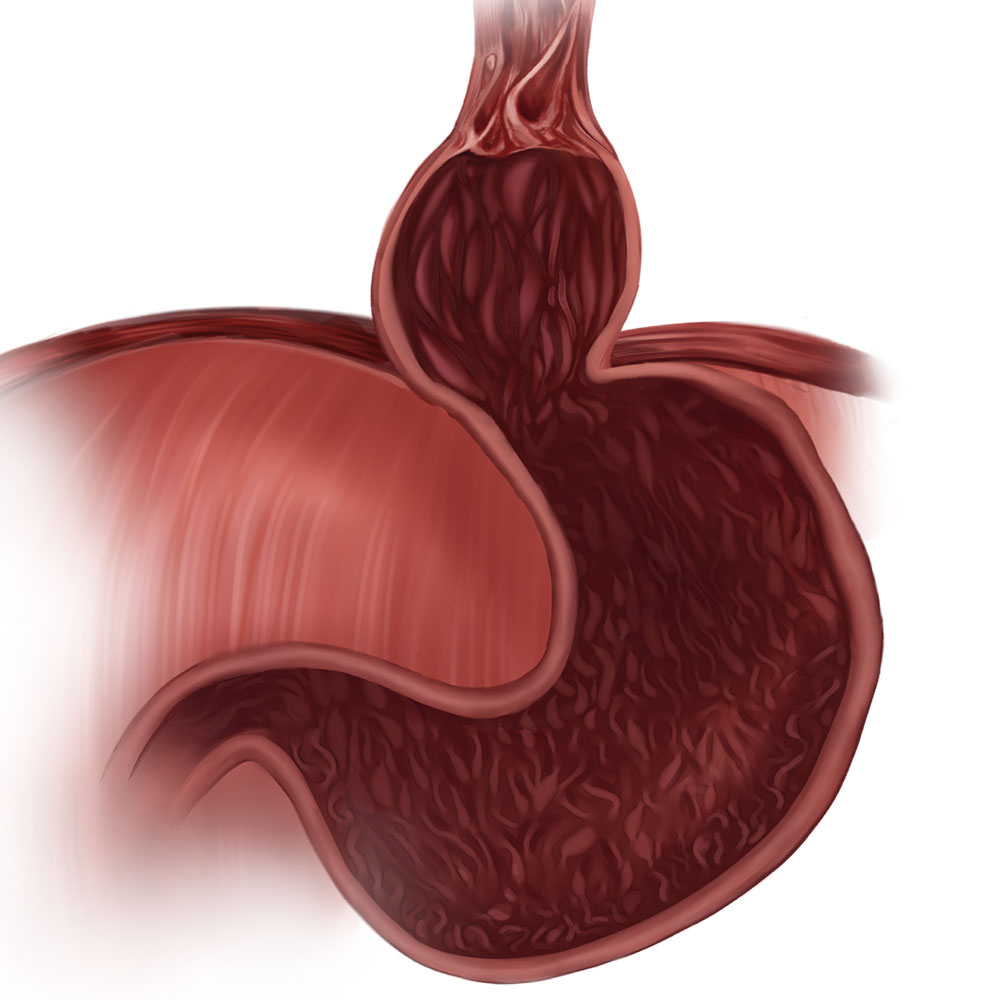

The root cause of acid reflux for many patients is a change in their anatomy where the stomach pushes through the diaphragm into the esophagus. This is known as a hiatal hernia. Using minimally invasive robotic surgery techniques, the stomach is placed back in its normal position. Once the hiatal hernia is repaired, lasting relief from GERD often requires repair of the valve that separates the stomach and esophagus. This takes place in the second part of the cTIF procedure.